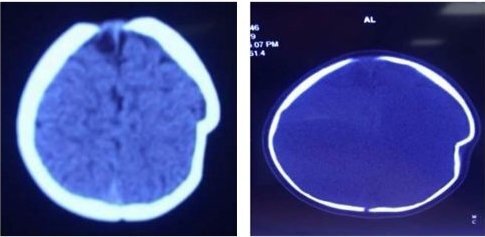

Bé gái ngã từ độ cao khoảng 1m xuống đất khiến sọ não bị lún sâu 1cm, phải nhập viện khẩn cấp để phẫu thuật.